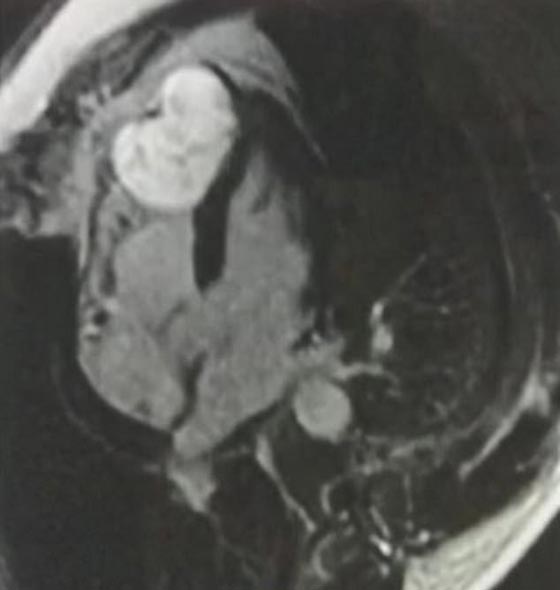

كتشف أطباء مفاجأة داخل قلب شاب عانى الألم مدة عشر سنوات في الصدر، بعد فحص قلبه بالتصوير بواسطة الرنين المغناطيسي. تبين من الفحص أن الشاب الأمريكي جاك كوهين الذي يبلغ من العمر 32 عاما، مصاب بأكبر ورم في القلب في العالم. وكان الأطباء قد شخصوا حالة كوهين، الذي يعاني من آلام الصدر، بأن ضغط دمه منخفض بشكل خطير، وذلك خلال اختبار الإجهاد، إلا أن التصوير بالرنين المغناطيسي، كشف أن كوهين لديه ورم بحجم كرة التنس في قلبه.

وقام الأطباء بإجراء جراحة قلب مفتوح للشاب من أجل إزالة الورم النادر للغاية، قبل 6 أشهر. وقال أطباء اختصاصيون في المركز الطبي، بجامعة كولومبيا الأمريكية، أن هذه أول مرة يشاهدون فيها مثل هذه الحالة. وصرح كوهين أنه كان يعاني من حرقان وثقل في صدره سبب له شعورا بالغثيان، وعدم القدرة على التنفس، بعد ممارسة الرياضة، وذلك منذ دراسته في الكلية، ووصف له الأطباء، تناول الأدوية المضادة للحموضة.

وأضاف أن الأطباء أخبروه أنه كان يعاني من حرقة في المعدة، أو ربما ضغط الدم المرتفع، وقبل 6 أشهر، ذهب إلى اختبار ضغط القلب، في حين تم رصد معدل ضرباته، والإيقاع، وضغط الدم عن كثب، وبعد 12 دقيقة من الهرولة الخفيفة، انخفض ضغط الدم بشكل كبير، وبنقله إلى غرفة الطوارئ في أحد المستشفيات، وبعد التصوير بالرنين المغناطيسي، اكتشف الأطباء الورم في قلبه.